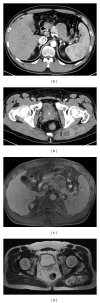

Extraskeletal mesenchymal chondrosarcoma is rare and metastasis to the pancreas is extremely rare, with only four cases reported in the literature. The therapeutic effectiveness of chemotherapy remains uncertain. We report a 39-year-old man with extraskeletal mesenchymal chondrosarcoma of the buttock, who had metastases to the pancreas, bones, and lung. He underwent distal pancreatectomy, resection of the buttock tumor, and chemotherapy. He had a good response to chemotherapy and survived for about 3 years after surgery.